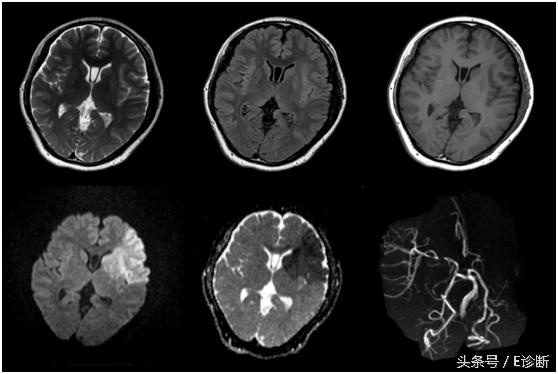

左侧基底节区亚急性期脑梗死,发病7天,T1WI为稍低信号,T2WI及flair像为高信号,DWI为高信号,ADC图为等信号,MRA示左侧大脑中动脉闭塞。